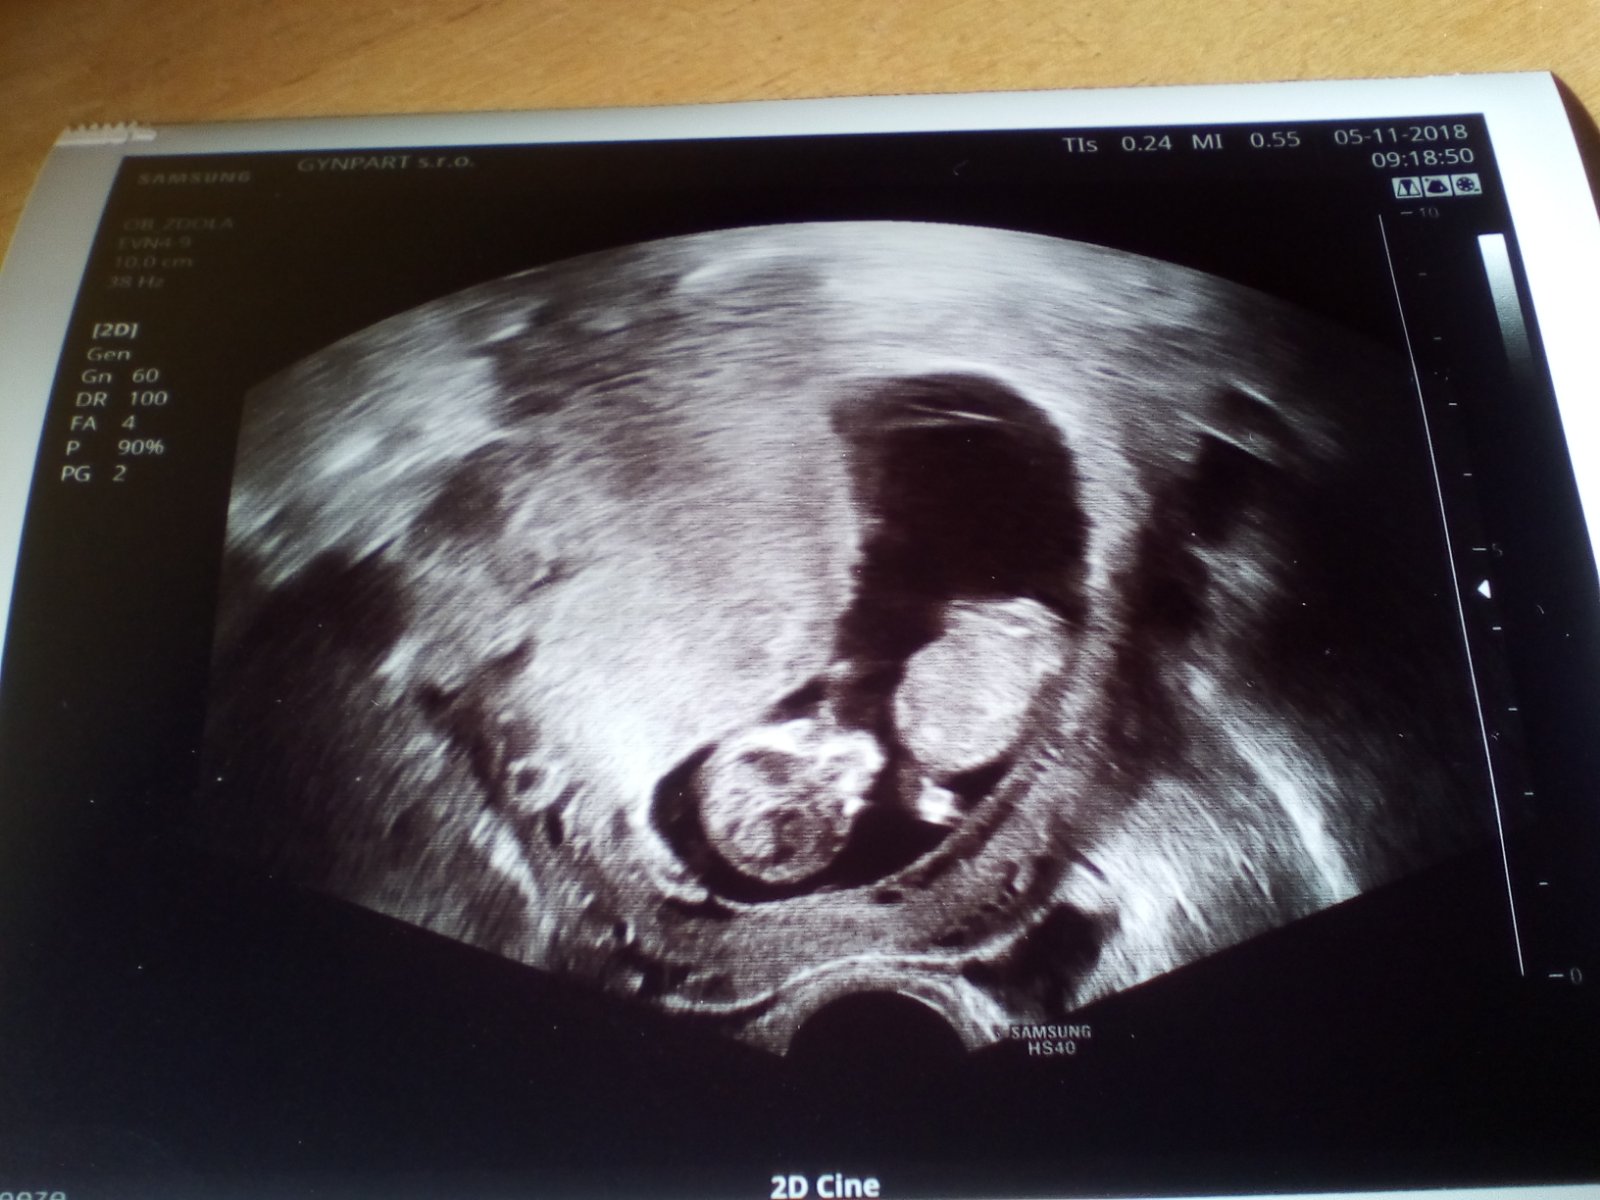

Ahoj devcata,tak jsem.byla na krvi zase...mam.si volat odpo...rekla ze ted vubec neresi cystu ale to.vysoke hcg..ze jsou mozne dve diagnozy,ale ze mola to s nejvetsi pravdepodobnosti nebude,ze ma vysledky z odberu z nemocnice a ze tam nebyla...a to druhe co mi hrozi nerekla at zad nehledam katastroficke scenare...pekny...modlim se at to.klesne...😢😢😢ale dnes me.hrozne boli prsa...a porad neco mele o.vylouceni mimodelozniho,ale to.nechapu,vzdyt mimi bylo v deloze to jsme videly jasne??